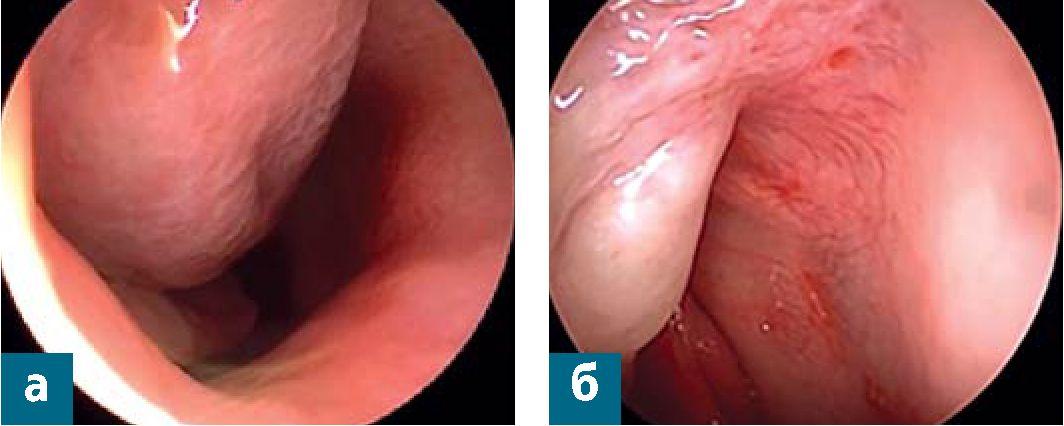

Сосудистое сплетение зоны Kisselbachi не расширено. Дыхание через нос затруднено. Слизистая оболочка полости носа розовая, чистая, не отечна; справа - визуализируется образование бледно-розового цвета, округлой формы, мягкой консистенции, интактное при воздействии инструментом, обтурирующее общий и средний носовые ходы (рис. 5), слева - общий носовой ход необозрим в связи с искривлением перегородки носа. Области проекции околоносовых пазух визуально не изменены, при пальпации и перкуссии безболезненны.

Рис. 5. Эндоскопическая фотография образования правой половины носа до хирургического лечения: а - образование сдавливает нижнюю носовую раковину; б - место крепления образования в правой половине полости носа